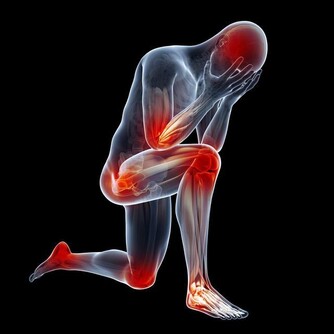

從功能上看,筋結會使關節活動範圍減小,轉頭受限,彎腰困難,抬腿彎膝不如從前。筋結壓迫神經造成疼痛,壓迫血管造成供血不足,筋脈失養,麻木抽搐,以及內科疾病等一系列病症……

人老先老腿,腿上的筋結多了會引起很多的問題,我們在正常行走或在上下樓梯時,突然感覺膝關節吃不住勁,腿發軟,差點跪下,很多內科疾病也和腿上的筋結有關。

我們可以用手指在內外膝眼二個位置按揉,會發現手下有咕嚕咕嚕的感覺,膝關節過伸或勞累後疼痛,這就是膝蓋筋結。